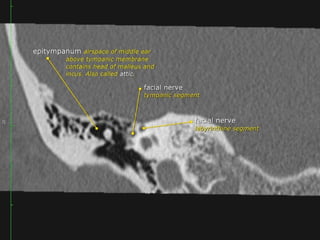

Middle Ear

 Epitympanum (attic):

Middle ear above line from

scutum tip to tympanic

 Mesotympanum: Middle

ear proper

 Hypotympanum: Shallow

trough in floor of ME

Three compartments in coronal plane.

• A line drawn from lower edge of the scutum to the tympanic

portion of the facial nerve -epi/mesotympanum.

• parallel to the floor of the external auditory canal

meso/hypotympanum

Anterior tympanic level

The TM may be identified as a thin filamentous

structure extending from the scutum superiorly and

coursing parallel to the plane of the long process of the

malleus to attach to the limbus inferiorly.

The head and neck of the malleus can be seen in the

epitympanic space, with the tendon of the tensor

tympani muscle attaching to neck.

The labyrinthine and tympanic segments of the facial

nerve are seen as two lucencies superior to the

cochlea.